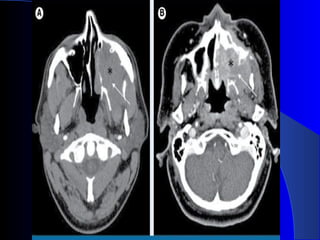

Case 3

Glomus Tumor

Glomus jugulare CT/MRI Findings:

• Center: jugular foramen

• Limit: hyoid bone

• Enhance w/ contrast

• Salt and pepper appearance on MRI

• Bone erosion

Origin:

• Chemoreceptor cells

Location:

• 10% multiple

• glomus jugulare: jugular bulb

• glomus tympanicum: cochlear promontory

Clinical:

• Pulsatile tinnitus

• Hearing loss

• arrythmia, BP fluctuation

• #59 CT imaging demonstrates the extent of bony destruction (white and black arrows) by the tumor. The normal jugular foramen on the left (arrow head) is shown for comparison.

• #60 Salt and pepper: multiple low signal intensity areas = flow voids in tumor. When large- erode bone.

• #61 Glomus tumors arise from chemoreceptor cells. These tumors are slow-growing hypervascular tumors that usually occur in the temporal bone. Location: read slide- check other places for them b/c = multiple. E.g. Carotid body Patients usually present with gradual hearing loss, unilateral pulsatile tinnitus, and lower cranial nerve palsies. Approximately 1-3% of gangliogliomas produce catecholamines, so can get arrythmia, BP fluctuation. May be locally invasive but rarely metastasize.